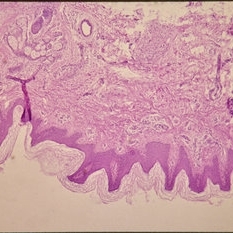

Histopathology of Linear Sebaceous Nevus Syndrome

Histopathology of Linear Sebaceous Nevus Syndrome

Feb 20 2015 by H. Michael Lambert, MD

Histopathology of linear sebaceous nevus syndrome.

Condition/keywords: histopathology, linear nevus sebaceous syndrome